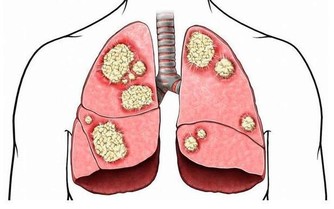

適量多曬太陽能幫助人體製造維生素D,而研究表明維生素D有抗癌作用。